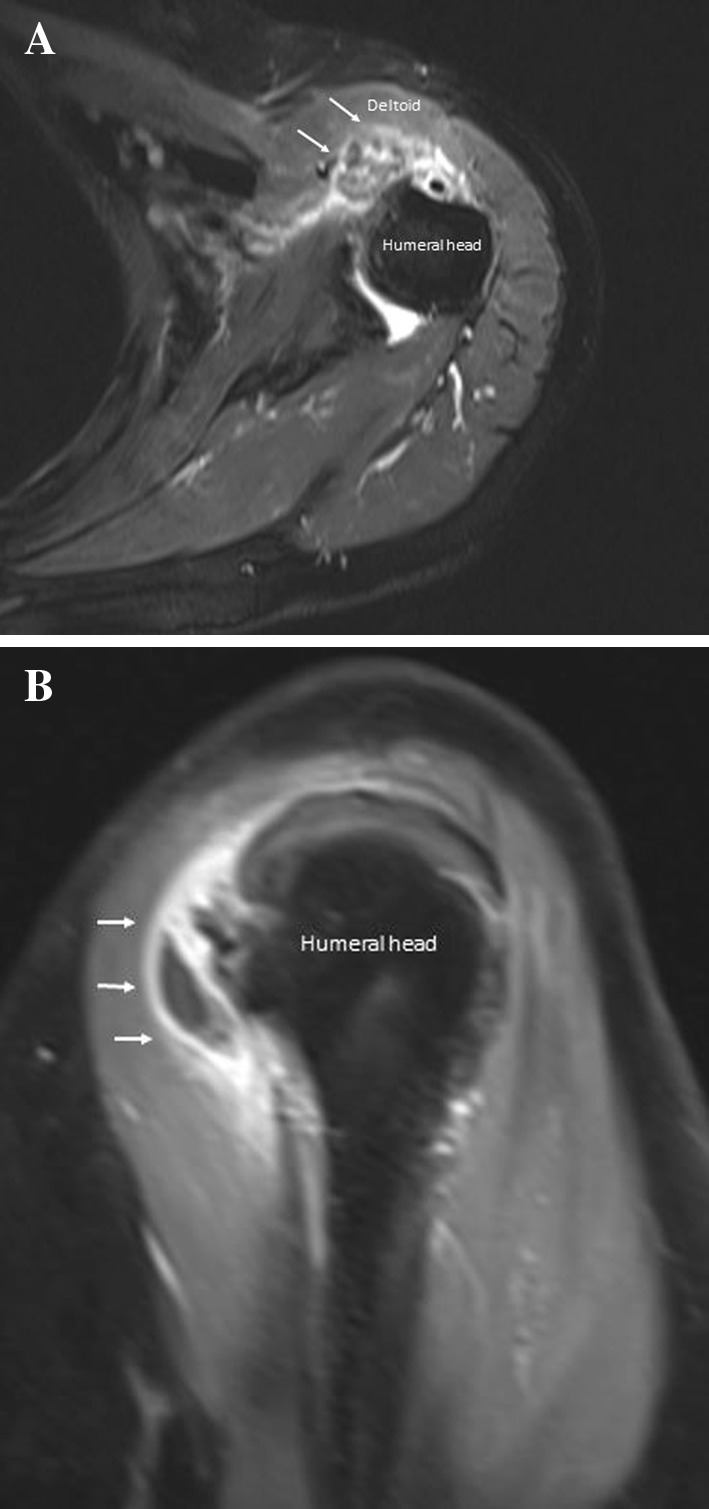

Fig. 4.

Calcium-related osteitis. Ultrasonography shows hyperchoic spots (calcium) (arrows) within humeral head erosion (a, b)

Sonographic diagnosis of intraosseous loculation from calcifying tendinitis is difficult since US has intrinsic limitations in the assessment of bone. However, with US, it is possible to depict irregularities of cortical outlines, focal bone erosions of the greater tuberosity and multiple small calcifications inside the cortical erosions along with the rotator cuff tendon (Fig. 4) (movies 2, 3); these findings should make the lesion suspected if the patient complains of intense pain without previous injury, but require confirmation with other imaging modalities, including radiography, computed tomography (CT) (Fig. 5) and magnetic resonance (MR) imaging (Fig. 6).